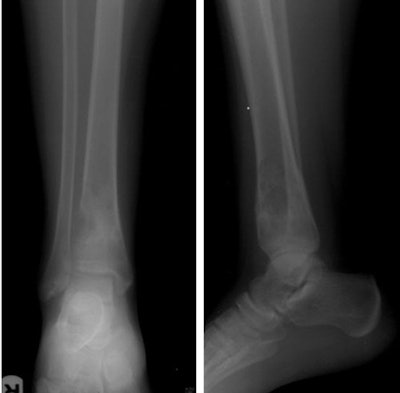

In all, 49 patients including 23 men and 15 women (mean age 33.7 years, range 4-77 years) underwent image-guided biopsies. Imaging in the cohort included radiography, CT, and MRI, and the study team categorized the records according to the location of the host bone, presence or absence of an extraosseous soft-tissue component (usually at MRI), and imaging nature of the lesion matrix (usually at CT) including lytic, sclerotic, or mixed lytic and sclerotic.

Cross-sectional imaging showed an extraosseous component in about half (26/49) patients, which facilitated biopsy and obviated the need for cortical breach, the authors wrote. The other 23 patients had completely intraosseous lesions that required more aggressive efforts to reach the lesion, the study team wrote.

Based on imaging findings at CT and x-ray, initial diagnostic yield was higher for mixed lesions (94%), followed by sclerotic (89%) and lytic (83%) lesions, according to the authors. As for the completely intraosseous lesions, the diagnostic yield was 74%, while the presence of extraosseous soft-tissue components raised the diagnostic yield to 100% in 26 cases.